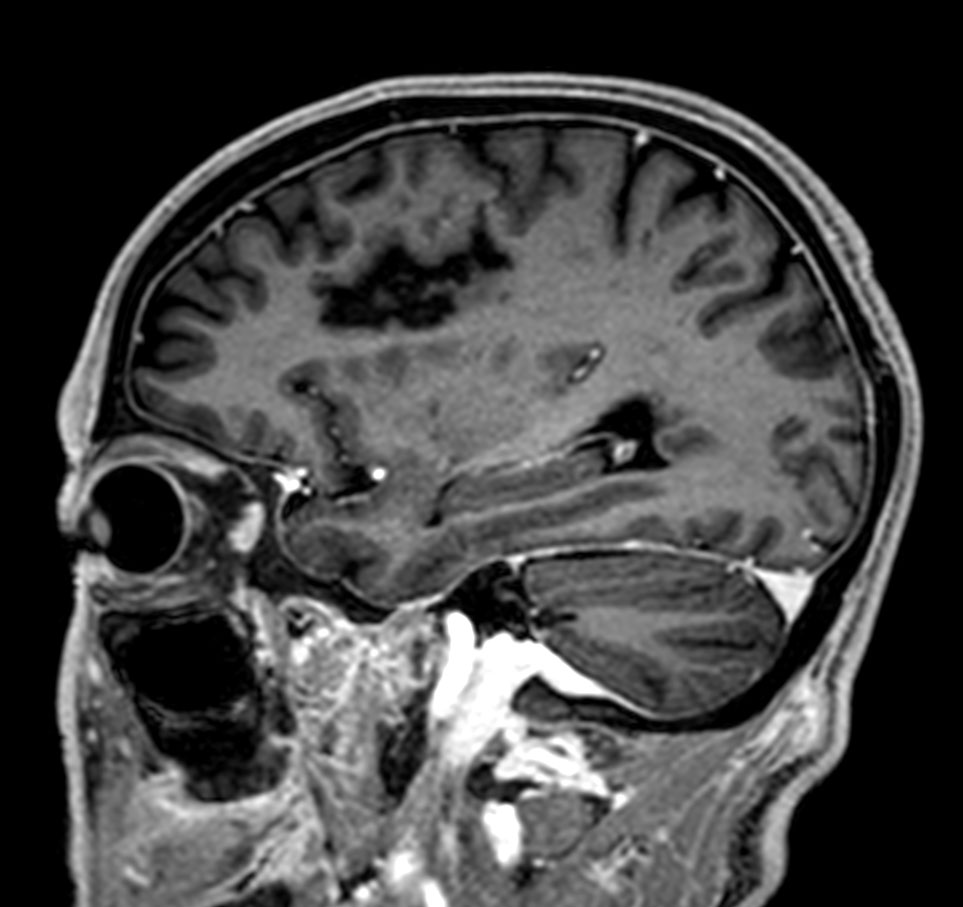

3D T1w mDIXON XD Compressed SENSE

-

3D T1w mDIXON XD (reformat) Compressed SENSE